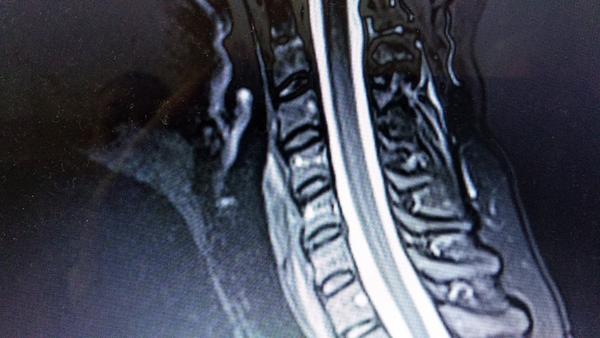

MR vyšetrenie chrbtice

Dobry den,vie mi niekto zodpovedat otazku ci pri MR th oblasti chrbtice mi zobrazi aj lopatky a oblast okolo nich..Mam neskutocne bolesti v tej casti..

@malinovka333 dakujem pekne za zodpovedanie..ide o to,ze viem,ze velakrat bolest z poskodenej platnicky moze zasahovat aj do lopatky,ale ja mam skor podozrenie,ze je to blokada alebo utlak nervu pod lopatkou..a neviem ci to teda toto vysetrenie ukaze..chodim k neurologicke a predpokladam,ze oni sa zaoberaju takouto bolestou aj v casti lopatiek..ktory iny odbornik?

@kacena4 dakujem pekne..a myslis ze ked mi dala ziadanku vysetrenia :th oblast a paraspin I.dx,otazka: vyl.struk leziu inu patologiu,tak by to mohla byt ta oblast okolo lopatky,lebo platnicka je podla mna zbytocna..